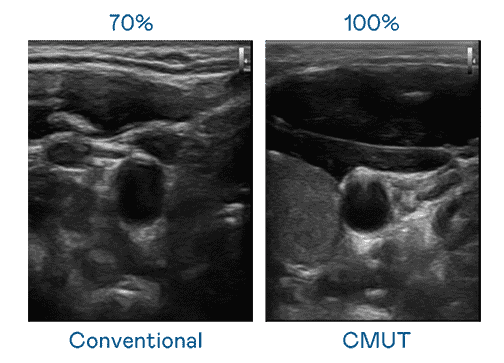

CMUT 技术是一种用电容式微机电元件来产生超音波讯号的技术。。。与传统 PZT 压电式技术相比,,,,CMUT 频宽增加 30%,,,,更宽频的超音波讯号让影像解析度大幅提升,,,,是实现高影像品质医疗超音波扫描、、、促进精准医疗发展的关键技术。。

大频宽带来超清晰影像

超音波影像的解析度高低,,首先取决于探头能发出的讯号频宽。。。优游UB8 CMUT 可提供高清晰的超音波讯号,,,,提供高频宽、、、高灵敏度、、影像纹理细节更高的超音波影像,,,协助医护人员缩短影像判读时间及利用精准的医疗影像进行诊断。。。